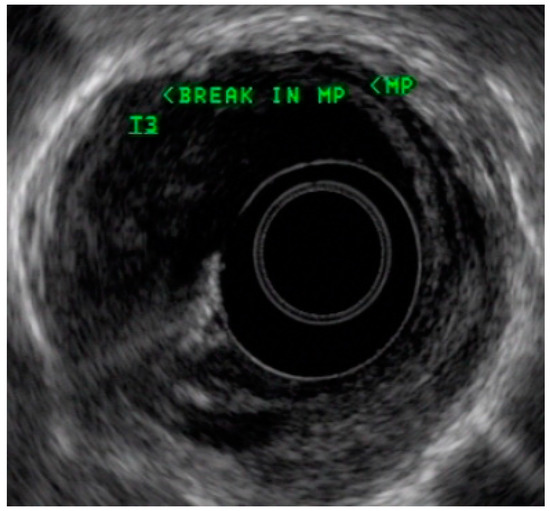

4.3. Endoscopic Ultrasound in Staging of Gastric Cancer